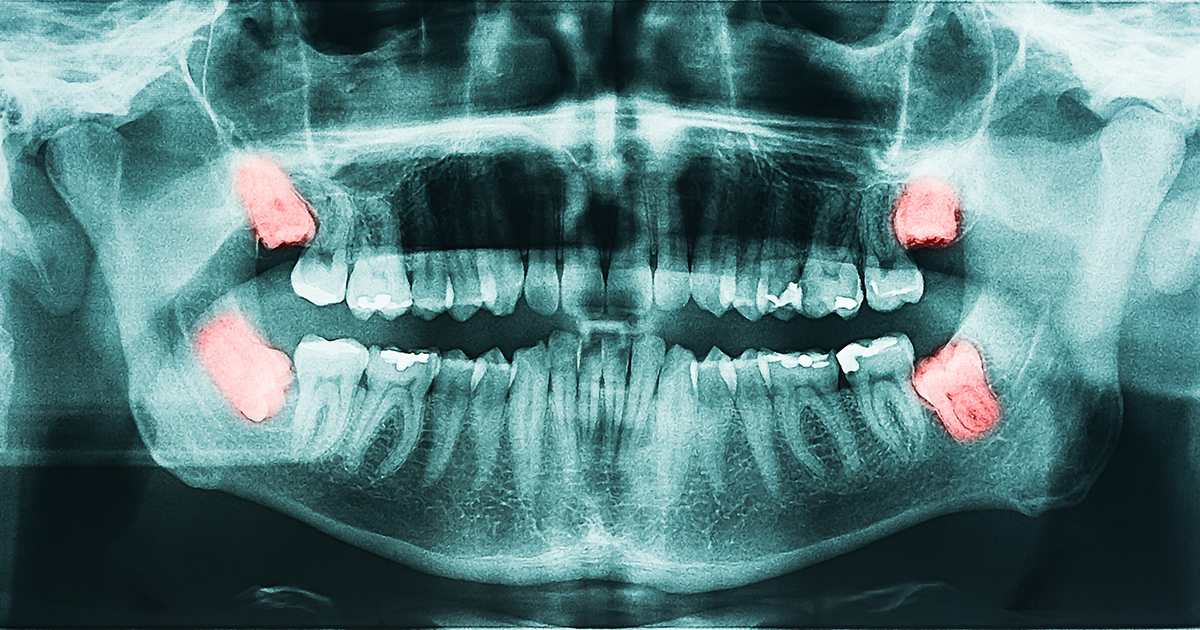

4 best treatments for a cracked tooth You can get a cracked tooth because of any reason. This includes grinding teeth at night, chewing hard food, and much more. When you notice this, the key is to seek help immediately. If you leave it for too long, the issue will get worse. Cracked teeth require…